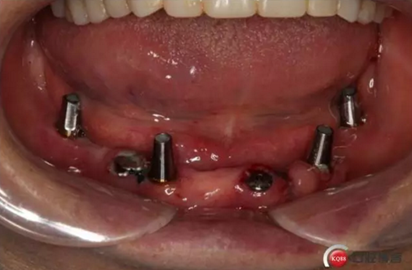

2)術(shù)前準(zhǔn)備及手術(shù)過(guò)程,測(cè)量血壓及血糖,簽種植知情同意書(shū);嚴(yán)格遵循無(wú)菌操作,局麻下采用微創(chuàng)技術(shù)于323436分別植入osstem4.0X10,4.0X10,4.5X7; 434446分別植入osstem4.0X1O,4.0X10,4.5X7.初期穩(wěn)定性均達(dá)到了35N.CM以上;嚴(yán)密縫合,止血,種植體位點(diǎn)和方向與設(shè)計(jì)一致。

4)三個(gè)月后行種植二期手術(shù)并拔除33殘冠,于34364346種植體接入成品基臺(tái),調(diào)改活動(dòng)義齒做一個(gè)改良式的套筒冠覆蓋義齒。